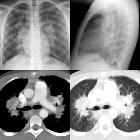

aspergillosis in a patient with chronic granulomatous disease

aspergillosis

chronic granulomatous disease